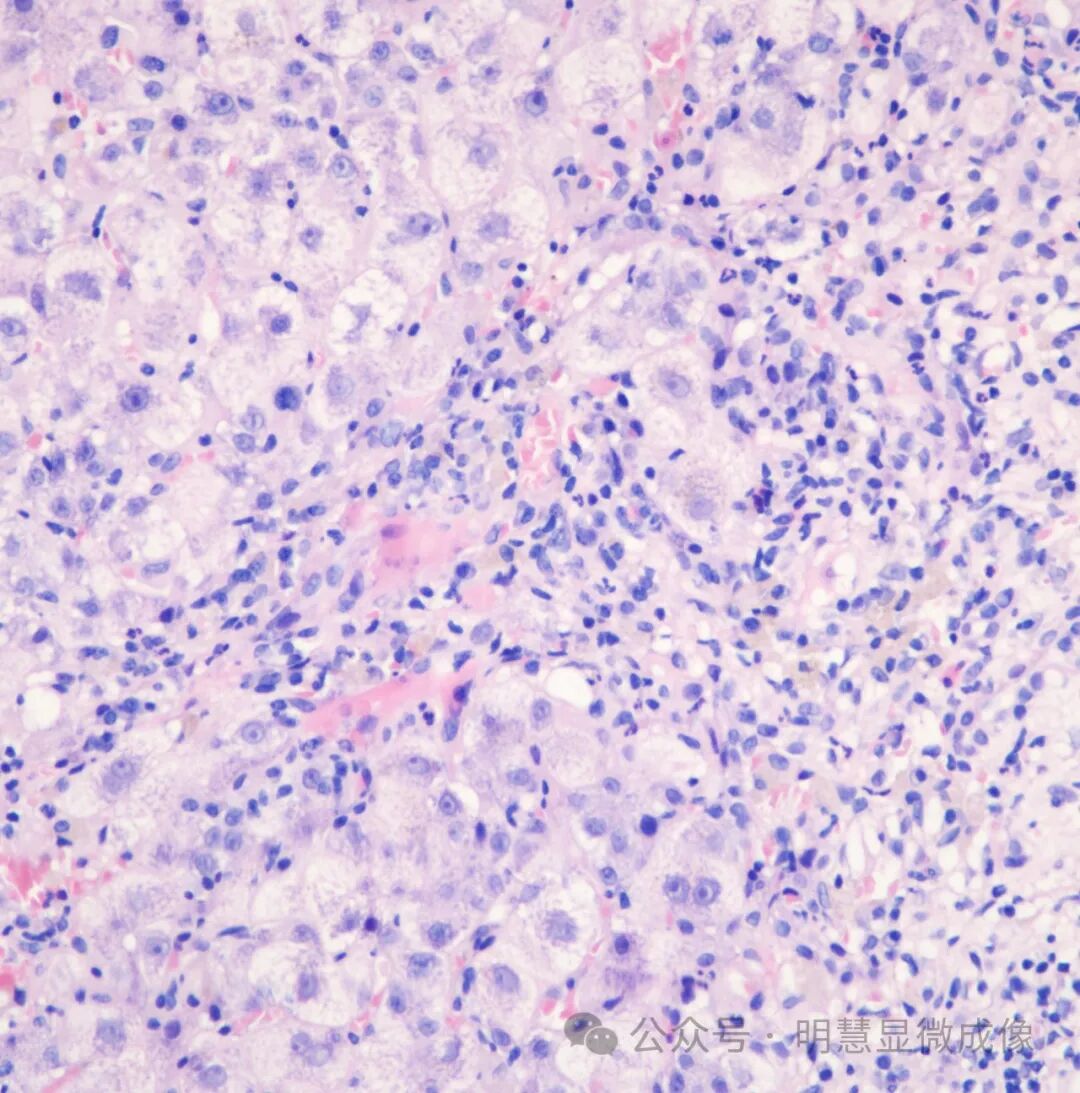

惭贬顿2000实拍效果图